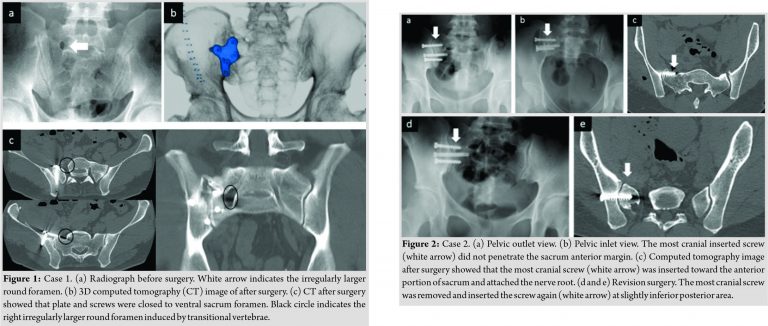

A 34-year-old man exhibited bilateral SIJ pain. The patient had LSTV Type Ⅳ, which manifested itself on the right side of the diarthrodial joint. A definitive diagnosis of SIJ pain was confirmed by SIJ injections. Fluoroscopy-guided local anesthetic injections performed on the right side of the diarthrodial joint were less effective than those in the SIJ. Conservative therapies performed for 9 months provided only temporary relief of his symptoms. His SIJ pain was more severe on the right. First, we attempted to fix the right SIJ using the anterior approach. Through a pararectal approach [6], the upper anterior surface of the SIJ was exposed between the psoas major muscle and the iliac muscle. A femoral nerve was retracted laterally toward the iliac muscle. The psoas major muscle was retracted medially to attach a plate and to insert screws on the sacrum side. Usually, the nerve root from the S1 ventral foramen was not exposed while retracting the psoas major muscle. However, in this surgery, the nerve root ran from the irregularly larger round foramen to the lateral side more than usual, and therefore, the nerve root was exposed (Fig. 1). Gently retracting the nerve with the psoas major muscle medially was needed to prevent nerve injury. After surgery, he complained of temporary right leg pain and numbness. We confirmed that the symptoms were radiculopathy by seeing complete pain relief just after selective nerve root block. Moreover, using selective nerve root contrast medium infiltration, we also confirmed that the nerve root did not come into contact with the plate.

Case 2

A 26-year-old woman had right SIJ pain and LSTV Type IIIb. A definitive diagnosis of SIJ pain was confirmed by SIJ injections. Conservative therapies done for 3 years and 2 months could not relieve her symptoms. We performed SIJ arthrodesis inserting three cancellous screws using the posterolateral approach. In this surgery, the sacral alar was thinner than usual due to sacral dysmorphism induced by LSTV. Therefore, the most cranial sacral vertebral body for the most cranial screw was relatively small. It was confirmed that all three screws had not penetrated the anterior margin of the sacrum under the inlet view. However, after surgery, the patient complained of the right buttock and lower extremity pain. Computed tomography (CT) imaging showed that the most cranial screw penetrated the anterior margin of the sacrum and attached to the nerve root. Immediately, the screw was removed and reinserted in a slightly posterior area (Fig. 2). In this case, the anterior margin of the small cranial portion of the sacrum was not shown clearly by inlet view during surgery due to overhanging the anterior margin of the caudal portion of the sacrum (Fig. 3).